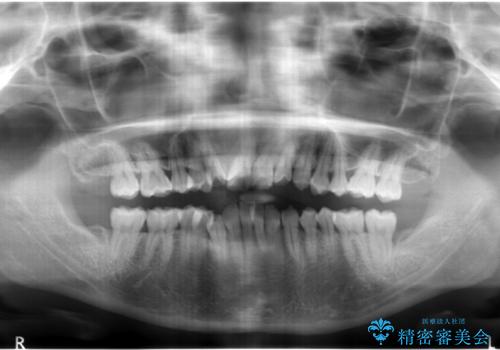

- 出っ歯を主訴に来院。

右上の犬歯が内側に生えていました。

右上の半分埋まっている犬歯を抜歯し、残り上下左右3本抜歯してワイヤー矯正を行いました。